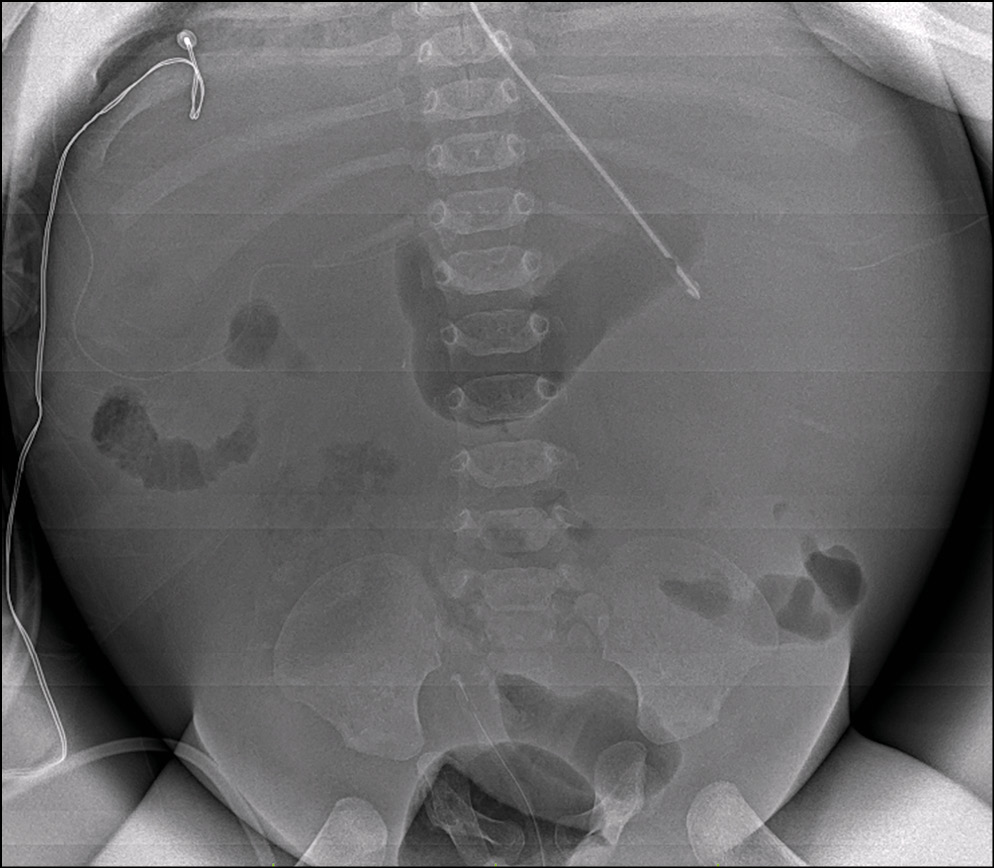

Для диагностики патологии брюшной полости важно отмечать пневматизацию петель кишки, наличие «уровней» жидкости, а также косвенных признаков асцита при выполнении исследования в горизонтальном положении пациента (рис. 5).

Рис. 5. Пациент с асцитом. Исследование выполнено при помощи микрофокусного рентгеновского аппарата.

Fig. 5. Patient with ascitis. Microfocus X-ray device.